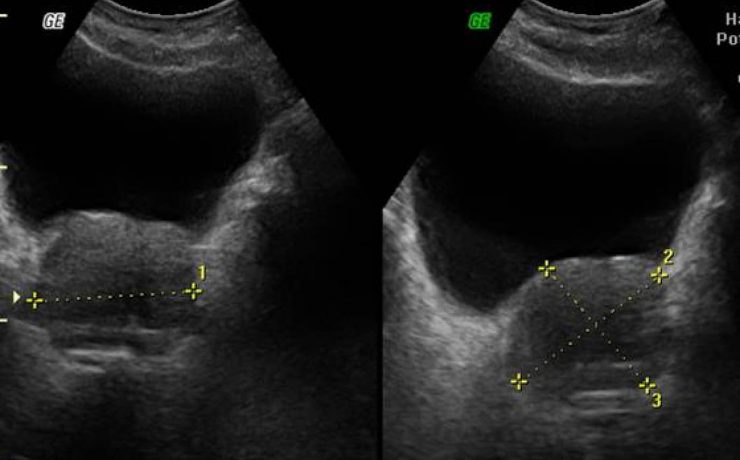

Correlación ultrasonográfica e histopatológica de los tumores de ovario

El cáncer de ovario, constituye el 2 % de las afecciones malignas de la mujer con una alta mortalidad, aproximadamente las dos terceras partes se presentan con lesiones muy avanzadas en el momento del examen imagenológico,1-4 trae por consecuencia una supervivencia menor de la paciente y un aumento del costo